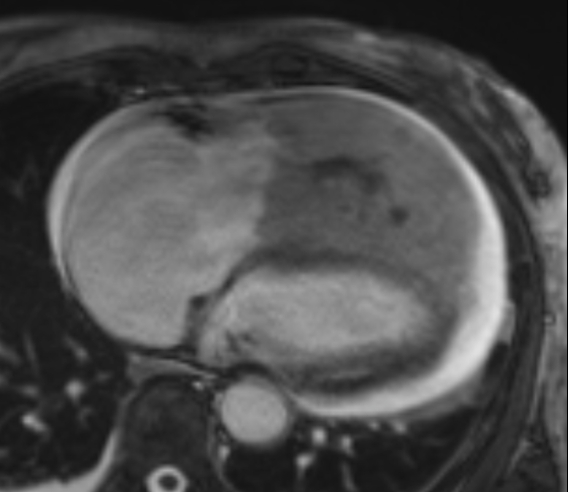

Transthoracic echocardiogram revealed a new 14cm right ventricular mass, a severely dilated right ventricle (RV) with severely reduced function, and a moderate pericardial effusion without tamponade physiology (Figure 1). The patient was transferred to our facility for cardiology and cardiothoracic surgery evaluation.